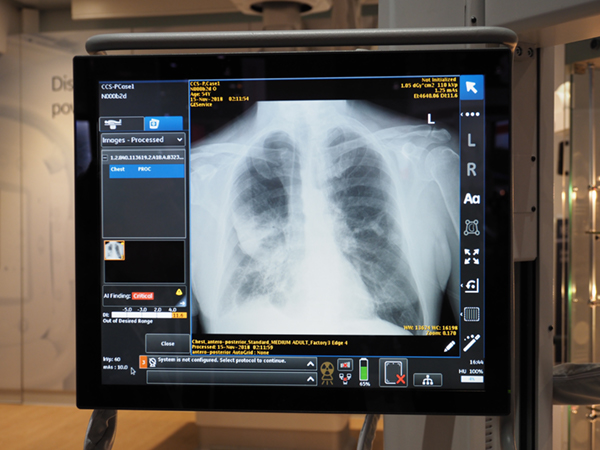

気胸を検出して診療を支援する

“Critical Care Suite”(FDA未承認)

GE Healthcare(GEヘルスケア)のX線撮影装置関連では,移動型X線撮影装置「Optima XR240amx」に搭載されるAIプラットフォーム“Edison”の診療支援システム“Critical Care Suite”(FAD未承認)が,FDA承認待ちの段階になっていることがアナウンスされた。ブース全体では,Edisonの技術が50近く紹介されているが,その中でも診断・検査支援システムとして,最も臨床現場の近くにやって来た技術と言えるのがCritical Care Suiteである。前回のRSNAでは参考出展であったが,製品化に向けて確実に開発を進めてきた。

一般的に,移動型X線撮影装置の検査では,担当技師は短時間で多くの撮影を行わなければならない。特に,救急での検査オーダも多く,被検者の状態も重篤な場合もあり,正確な撮影と速やかな読影が重要なカギを握る。そこで,Critical Care Suiteでは,撮影直後に気胸の有無を判定して,気胸の確信度などの判定結果を示すことで,速やかな治療への移行を支援する。気胸の判定のほかにも,ポジショニングに問題があった場合はアラートを出すため,診療放射線技師の教育にも役立てることができる。

気胸を検出して診療を支援する“Critical Care Suite”(FDA未承認)